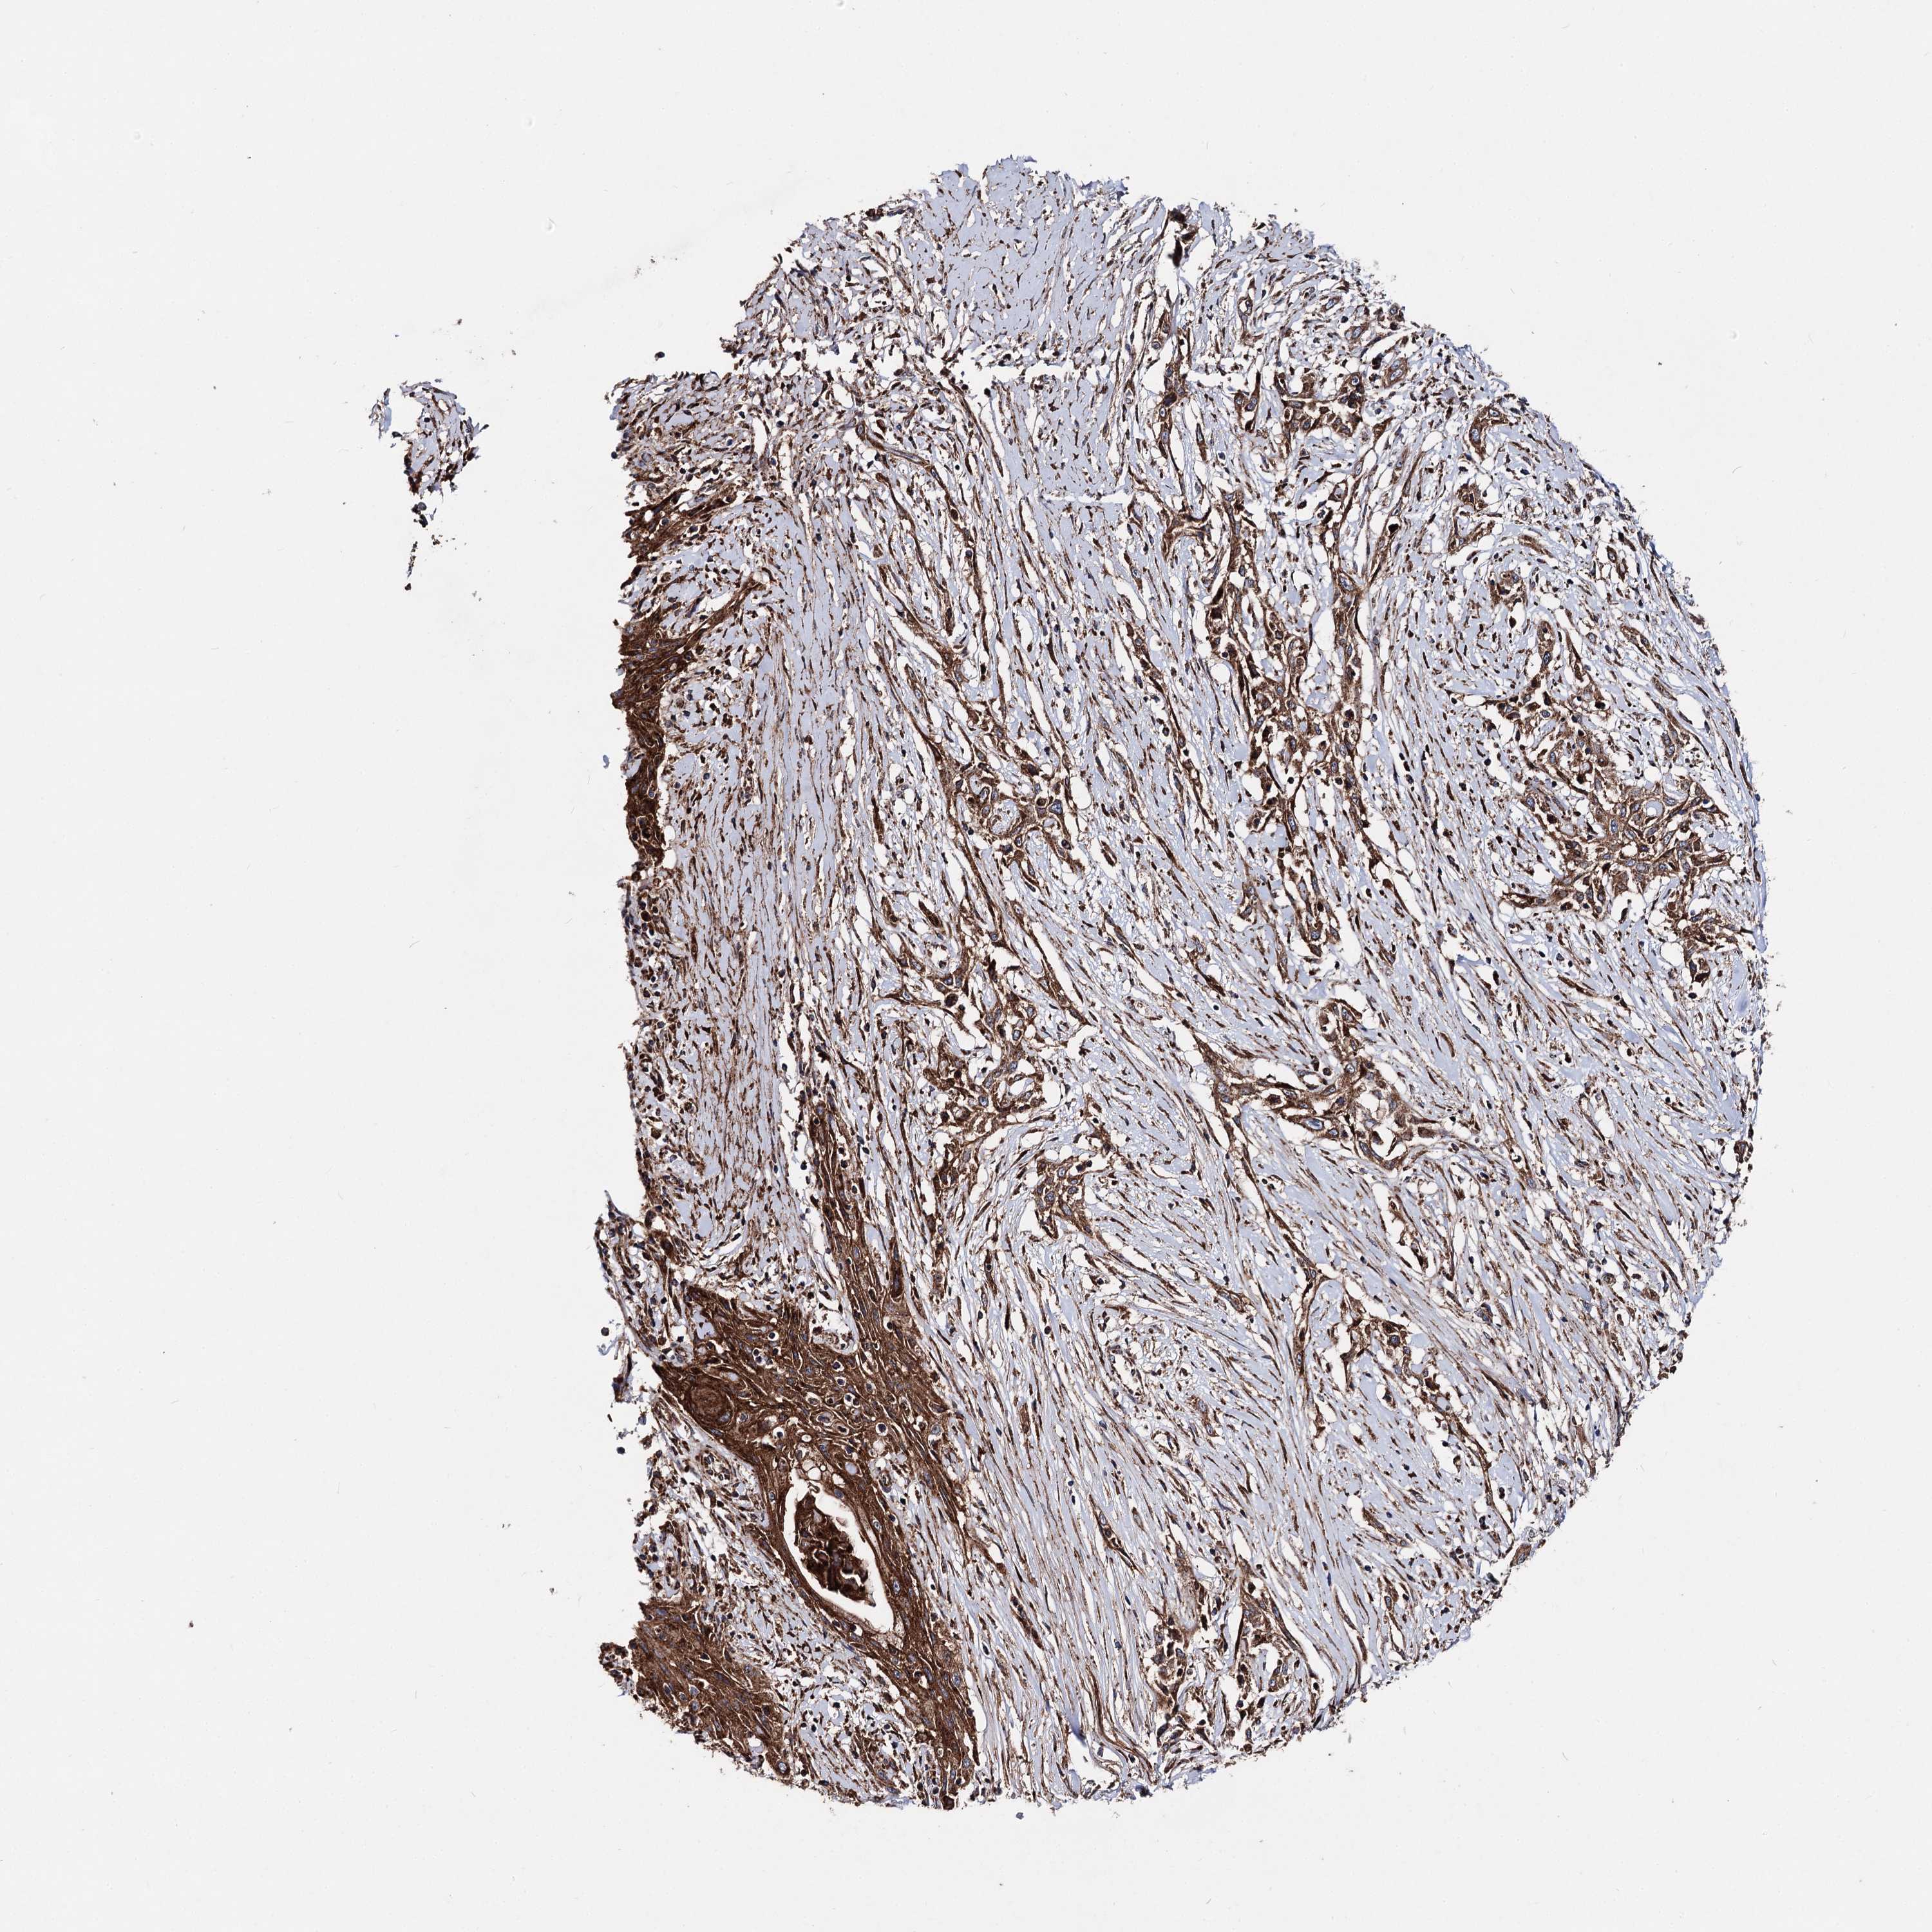

Basal cell and squamous cell cancer

SKIN CANCER - Protein expressioni

A mouse-over function shows sample information and annotation data. Click on an image to view it in a full screen mode. Samples can be filtered based on level of antibody staining by selecting one or several of the following categories: high, medium, low and not detected. The assay and annotation is described here.

Each image is clickable and will lead to virtual microscopy that enables deeper exploration of all samples and also displays staining intensity scores, fraction scores and subcellular localization as well as patient and tissue information for each sample.

Antibody HPA038694

Antibody HPA038695

Squamous cell carcinoma, NOS